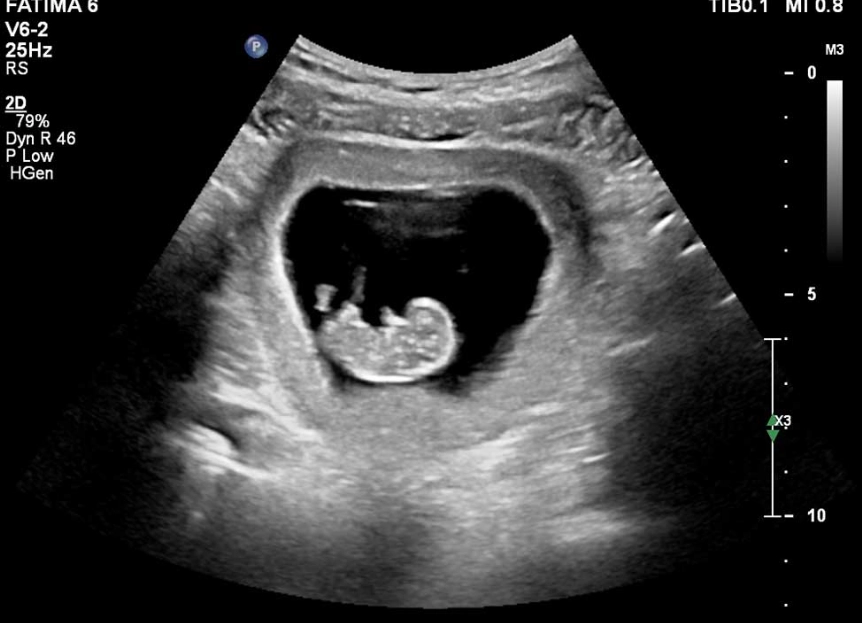

You'll lie back, the sonographer will apply some warm gel, and glide a transducer over your abdomen. If your uterus is still tucked behind your pelvic bone (common in first pregnancies), they might use a transvaginal probe for a clearer image. Don't stress; it's uncomfortable but not painful.

First, it confirms your due date with much greater accuracy. Early ultrasounds (before 14 weeks) are the gold standard for dating a pregnancy. They measure the baby from crown to rump (CRL). If this measurement differs by more than 5-7 days from your LMP date, your due date will be officially changed. I've had my own due date adjusted by 5 days based on this scan—it's incredibly common, especially if your cycles aren't a perfect 28 days.

Second, it's a major anatomy check. The sonographer is verifying that all the major structures are forming in the right place. They check the brain, the abdominal wall, the insertion of the umbilical cord, and the spine. Finding certain major issues early allows for more time for counseling, planning, and specialized care.

Third, it assesses your own anatomy. They look at your uterus and ovaries for any cysts or fibroids that could affect the pregnancy. They check the location of the placenta. Is it low-lying? That's something to monitor later.